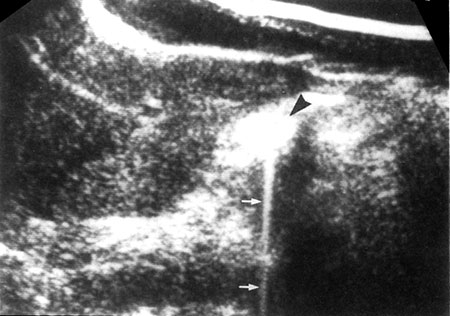

Section Thickness Artifacts

Section thickness artifacts are caused when the boundary between the wall of a cyst, gallbladder or urinary bladder and the structure containing fluids is not perpendicular to the interogating ultrasound beam. These causes appearance of false debris in echo free areas and presenting as unechoic objects as echogenic. This is because an interogating beam has finite thickness on its scans through the patient. Echoes are received that orginates not only from the centre of the beam but also from off centre. These are collapsed into, thin, two dimensional image, that is composed of an echo that have come from a not a very thin tissue volume scanned by the beam.

Hence echoes within the returning beam include from liquid as well as solid structure and averaged by the process or consequently the boundaries between solid tissues and fluid is seen as a low echogenic and indistinct structure. It can mimic sludge or layered material (concrements, blood clots) in the urinary bladder (Figs 1.19 and 1.20).

Fig. 1.19: Beam width artifact: The strong echoes from a pocket of gas in a pelvic gut loop (arrowhead) smear across the bladder (arrow)

Fig. 1.20: Beam width artifact: A weaker beam spread artifact misplaces echoes from the more reflective sinus tissues (arrow-head) into in renal cyst (arrow)